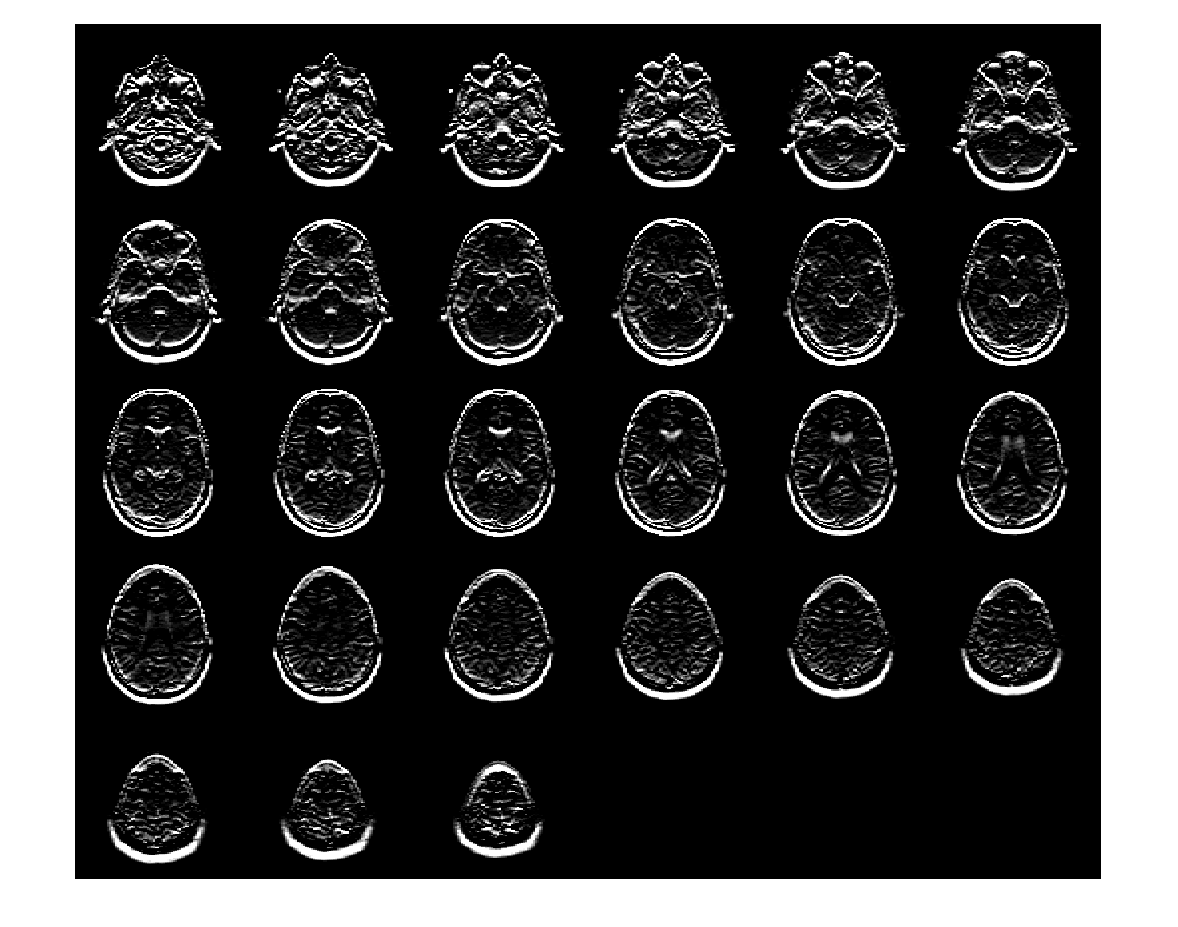

Загрузите 3-D полутоновый объем MRI. Отобразите плоскости объема.

load mristack;

montage(mristack,'BackgroundColor','w')

Figure contains an axes object. The axes object contains an object of type image.